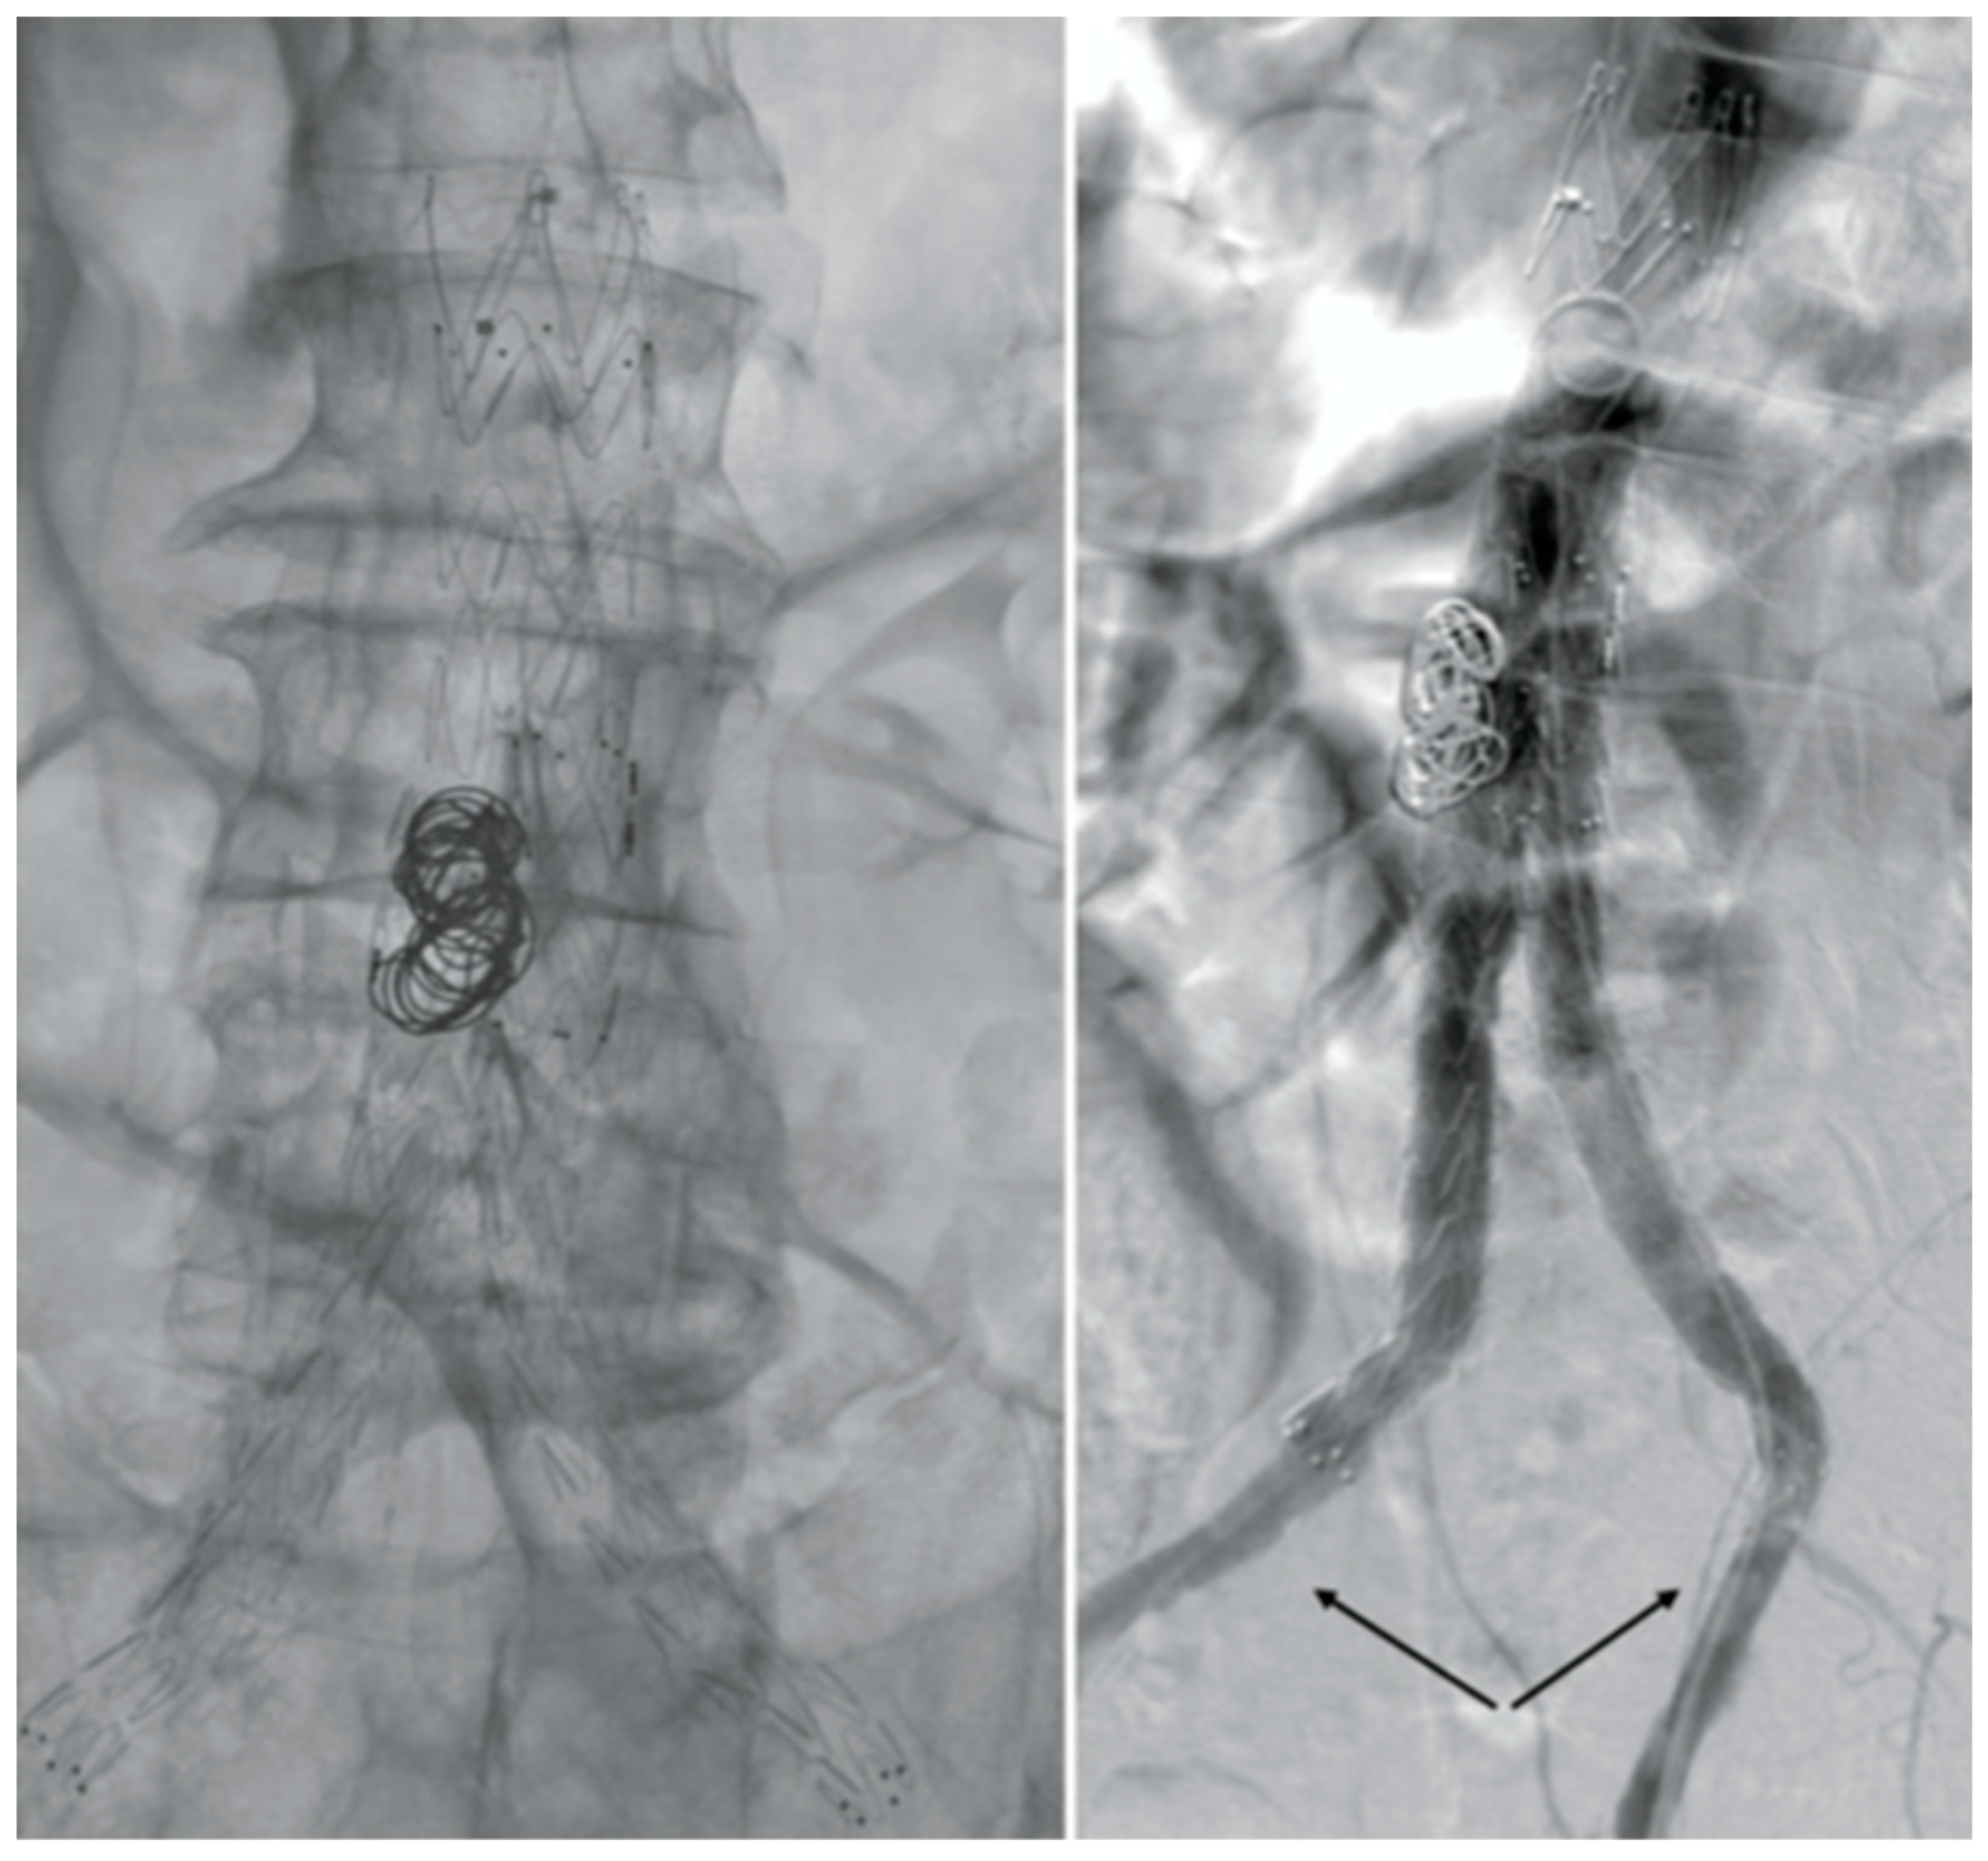

After consulting a team of interventional radiologists, an endovascular treatment with fibrinolytic agent infusion was preferred. Catheter directed thrombolysis with urokinase infusion (60000 IU/h) was started through bilateral percutaneous CFA access. No fabric’s infolding, stent fracture or stenosis of the native EIAs were noted (Figure 3).

Figure 3. Angiography images. No fabric’s infolding, stent fracture or stenosis of the native EIAs were noted.